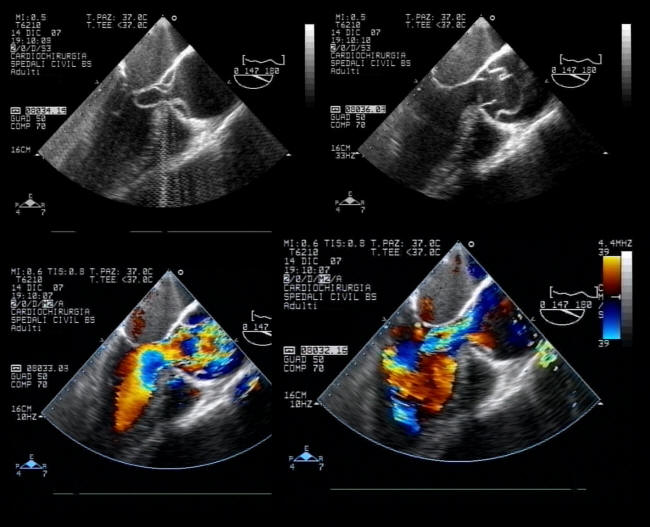

Colour Doppler echocardiogram In Anterior Wall myocardial ...

Colour Doppler echocardiogram in anterior wall myocardial infarction (AWMI). Description at: https://cardiophile.org/colour-dopple ... View Video